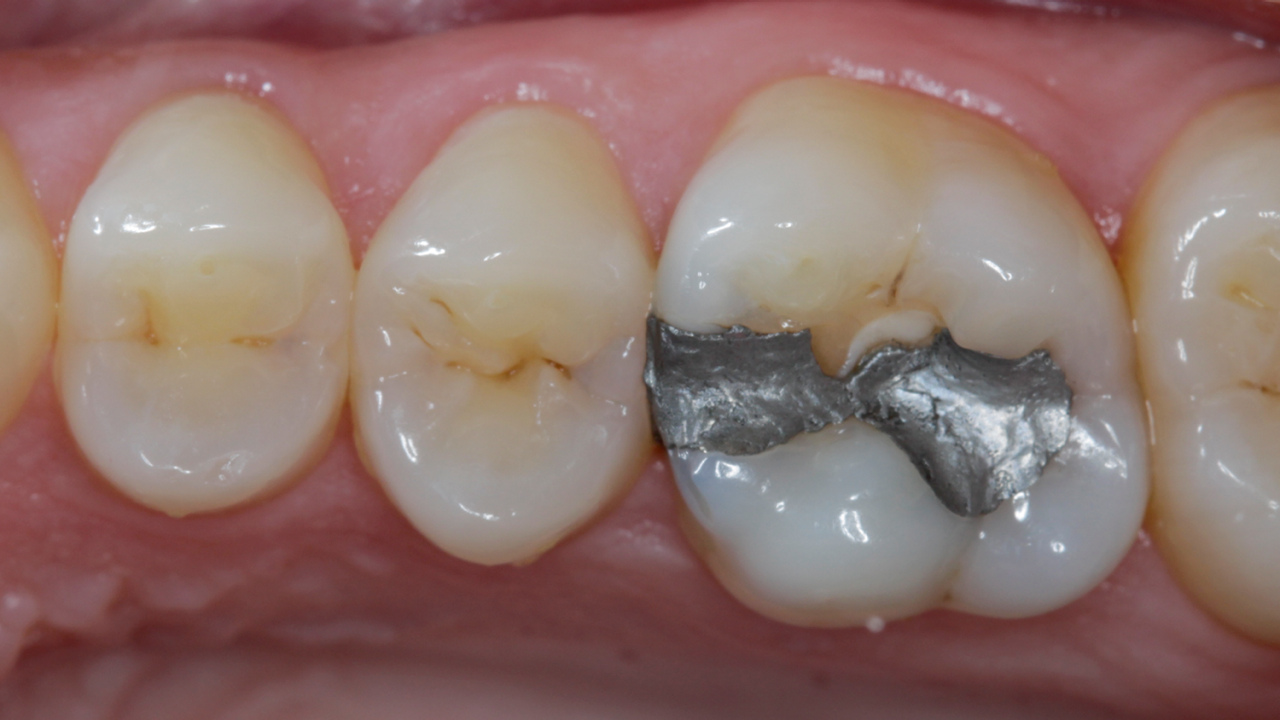

Disto-occlusal Composite Resin Restoration

Case: A 38 year old male patient presented a failed Class II DO composite restoration on a lower molar. After radiographic and clinical examination, the patient was anesthetized, and the old failed restoration, as well as the caries lesion, was removed. The Class II DO cavity restoration was performed using an optimized approach.

Conclusion: In order to reduce the chance of post-operative sensitivity, the selective etching approach was used with a universal adhesive. For perfect to gap free composite adaptation, the low polymerization stress, self leveling, bulk-fill composite SDR flow+ was used. In addition, for accurate proximal contour and optimal creation of a tight contact point, the sectional matrix system Palodent V3 was used.